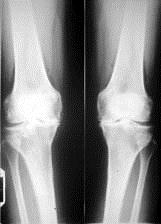

问题 病历摘要: 患者女性,65岁,双膝关节疼痛畸形,伸直受限10分钟,加重3个月。查体:双膝关节呈内翻畸形,双膝关节屈曲90受限,伸直受限,实验室检查正常,癤线见图: 该患者进行全膝关节置换术需掌握的手术原则是:

选项 A、掌握正确的骨水泥固定技术 B、保证骨组织切除后伸位或屈位股骨与胫骨之间的空隙宽度相同 C、保证股四头肌伸膝器的对线,使髌骨假体在股骨假体前方髌股关节面上滑动 D、不容许用骨切除的方法纠正关节的畸形 E、尽量少切除骨组织,缺损处可行植骨术 F、首先对膝内侧或外侧挛缩的软组织进行松解以纠正膝关节的对线,同时在伸屈膝关节时,要保持膝关节内、外、后侧软组织的张力平衡,必须先松解软组织后再进行骨组织切除